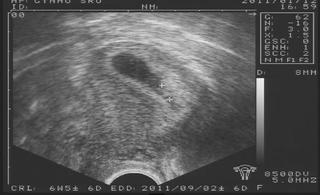

ahojte holky nestíhám dočítat, jen sjem hodila tabulku tk snad je ok, jdu se najíst, teď jsem přišla z kontroly a máme srdíčko 😀 😀 tak snad už bude vše ok, ale zarazil mľ mudra chce mě vidět až 22.2. to mi přijde straŠně pozdě to nevydržím 😒

furt kukám na fotečku, tak jsem tam vyčetla, že dle utz to je 6tt+5 takže o 3 dny starší než počítal mudra 🙂

avoj holky, du se nahlásit a koukam že du akorát, Madormi krásnej flíček 😵 😵 😵 gratuluju 🙂